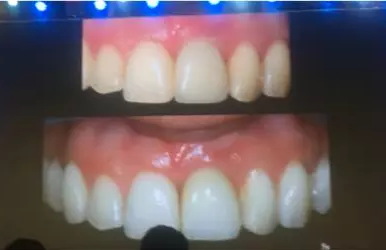

Prof. Carlo Maiorana展示了一例拔牙前聯(lián)合正畸治療獲得新骨形成的病例。該病例左上頜中切牙和側(cè)切牙需要拔除,x線顯示兩牙根距離較近、牙根頸部存在角形吸收,拔牙前通過正畸獲得新骨形成,然后拔牙即刻種植,終完成良好的牙冠修復(fù)。